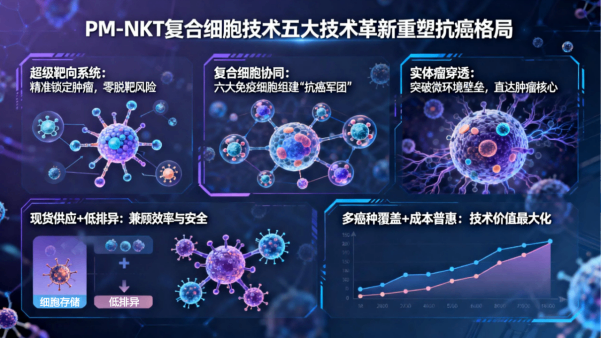

NK免疫疗法

NK免疫疗法

加强型免疫疗法

加强型免疫疗法

六大核心业务

国际领先六大肿瘤疗愈体系,确保每一位肿瘤患者得到超越预期的肿瘤疗愈,康复,终身健康保障服务。中美国际肿瘤连锁:郑州誉美肿瘤医院,武汉名逸肿瘤医院、博鳌华侨肿瘤医院。